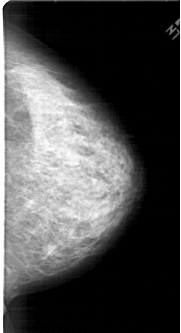

A_1453_1.LEFT_CC

LEFT_CC LINES 6421 PIXELS_PER_LINE 3391 BITS_PER_PIXEL 12 RESOLUTION 43.5 OVERLAY